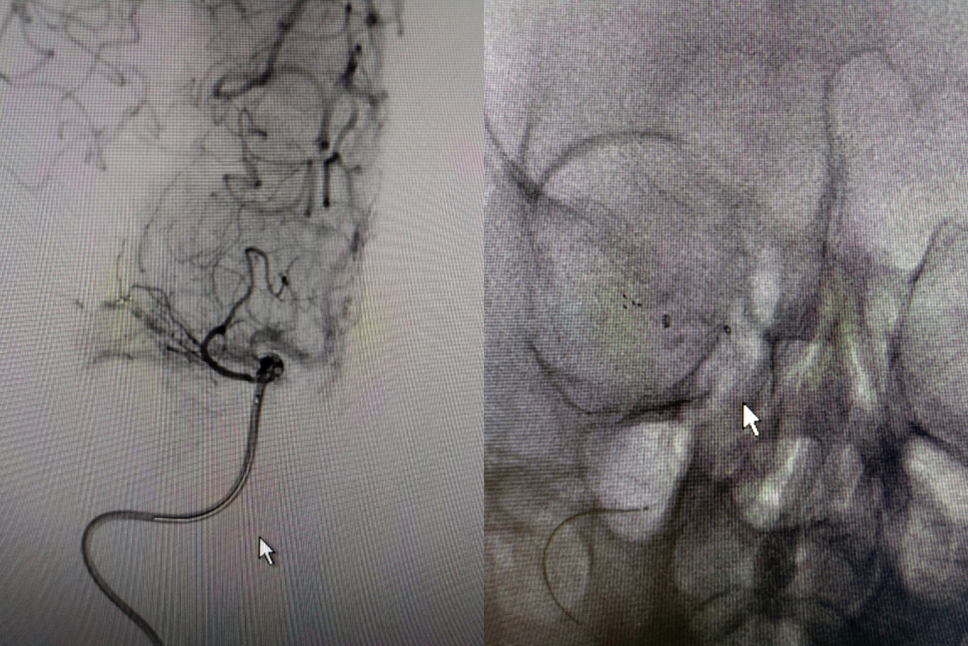

术后影像及检查

术后正位造影。

导丝怎么扩【载药时代 球扩天下】NOVA DES®颅内药物洗脱支架在大脑中动脉重度狭窄的应用二例!_https://www.jmylbn.com_新闻资讯_第30张

术后侧位造影

导丝怎么扩【载药时代 球扩天下】NOVA DES®颅内药物洗脱支架在大脑中动脉重度狭窄的应用二例!_https://www.jmylbn.com_新闻资讯_第31张